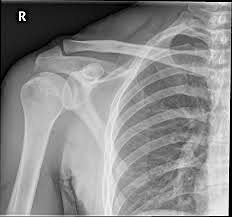

Anatomy of the shoulder will be detailed using plain film x-ray, MRI and ultrasound imaging, backed up by a practical session in the on-site pro-section lab.

The radiologists will cover the clinical indications for each imaging modality, normal imaging series and measurements, reporting terminology and indicators of pathology and trauma.

• Recognise normal anatomical appearance of the shoulder on x-ray and MRI

• Use and understand imaging terminology in relation to shoulder pathology

• Explain and integrate imaging findings to symptoms and diseases in shoulder patients

• Make appropriate referrals for a range of pathologies and trauma in the shoulder